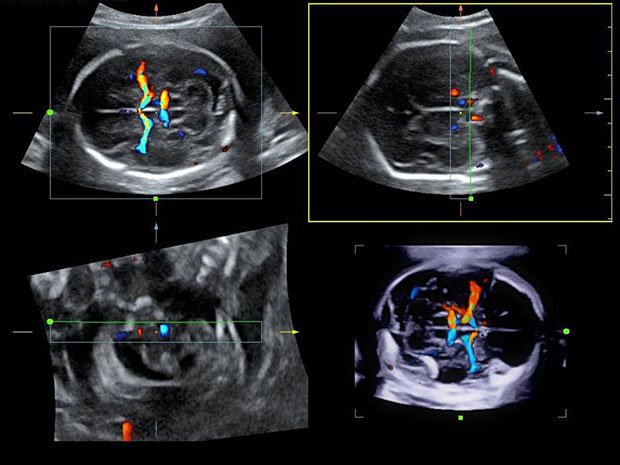

Инновационная технология 4D

4D УЗИ – это высокоинформативный ультразвуковой скрининг, при котором на монитор выводится не статичная картинка, а трехмерное изображение в режиме реального времени.

3D/4D УЗИ при беременности

4D УЗИ дает возможность разглядеть мельчайшие детали строения, например, пол ребенка, количество пальчиков на ручках и ножках. Если проводить 4 d диагностику на 32 неделе беременности, то можно увидеть мимику ребенка, как он улыбается или хмурится.